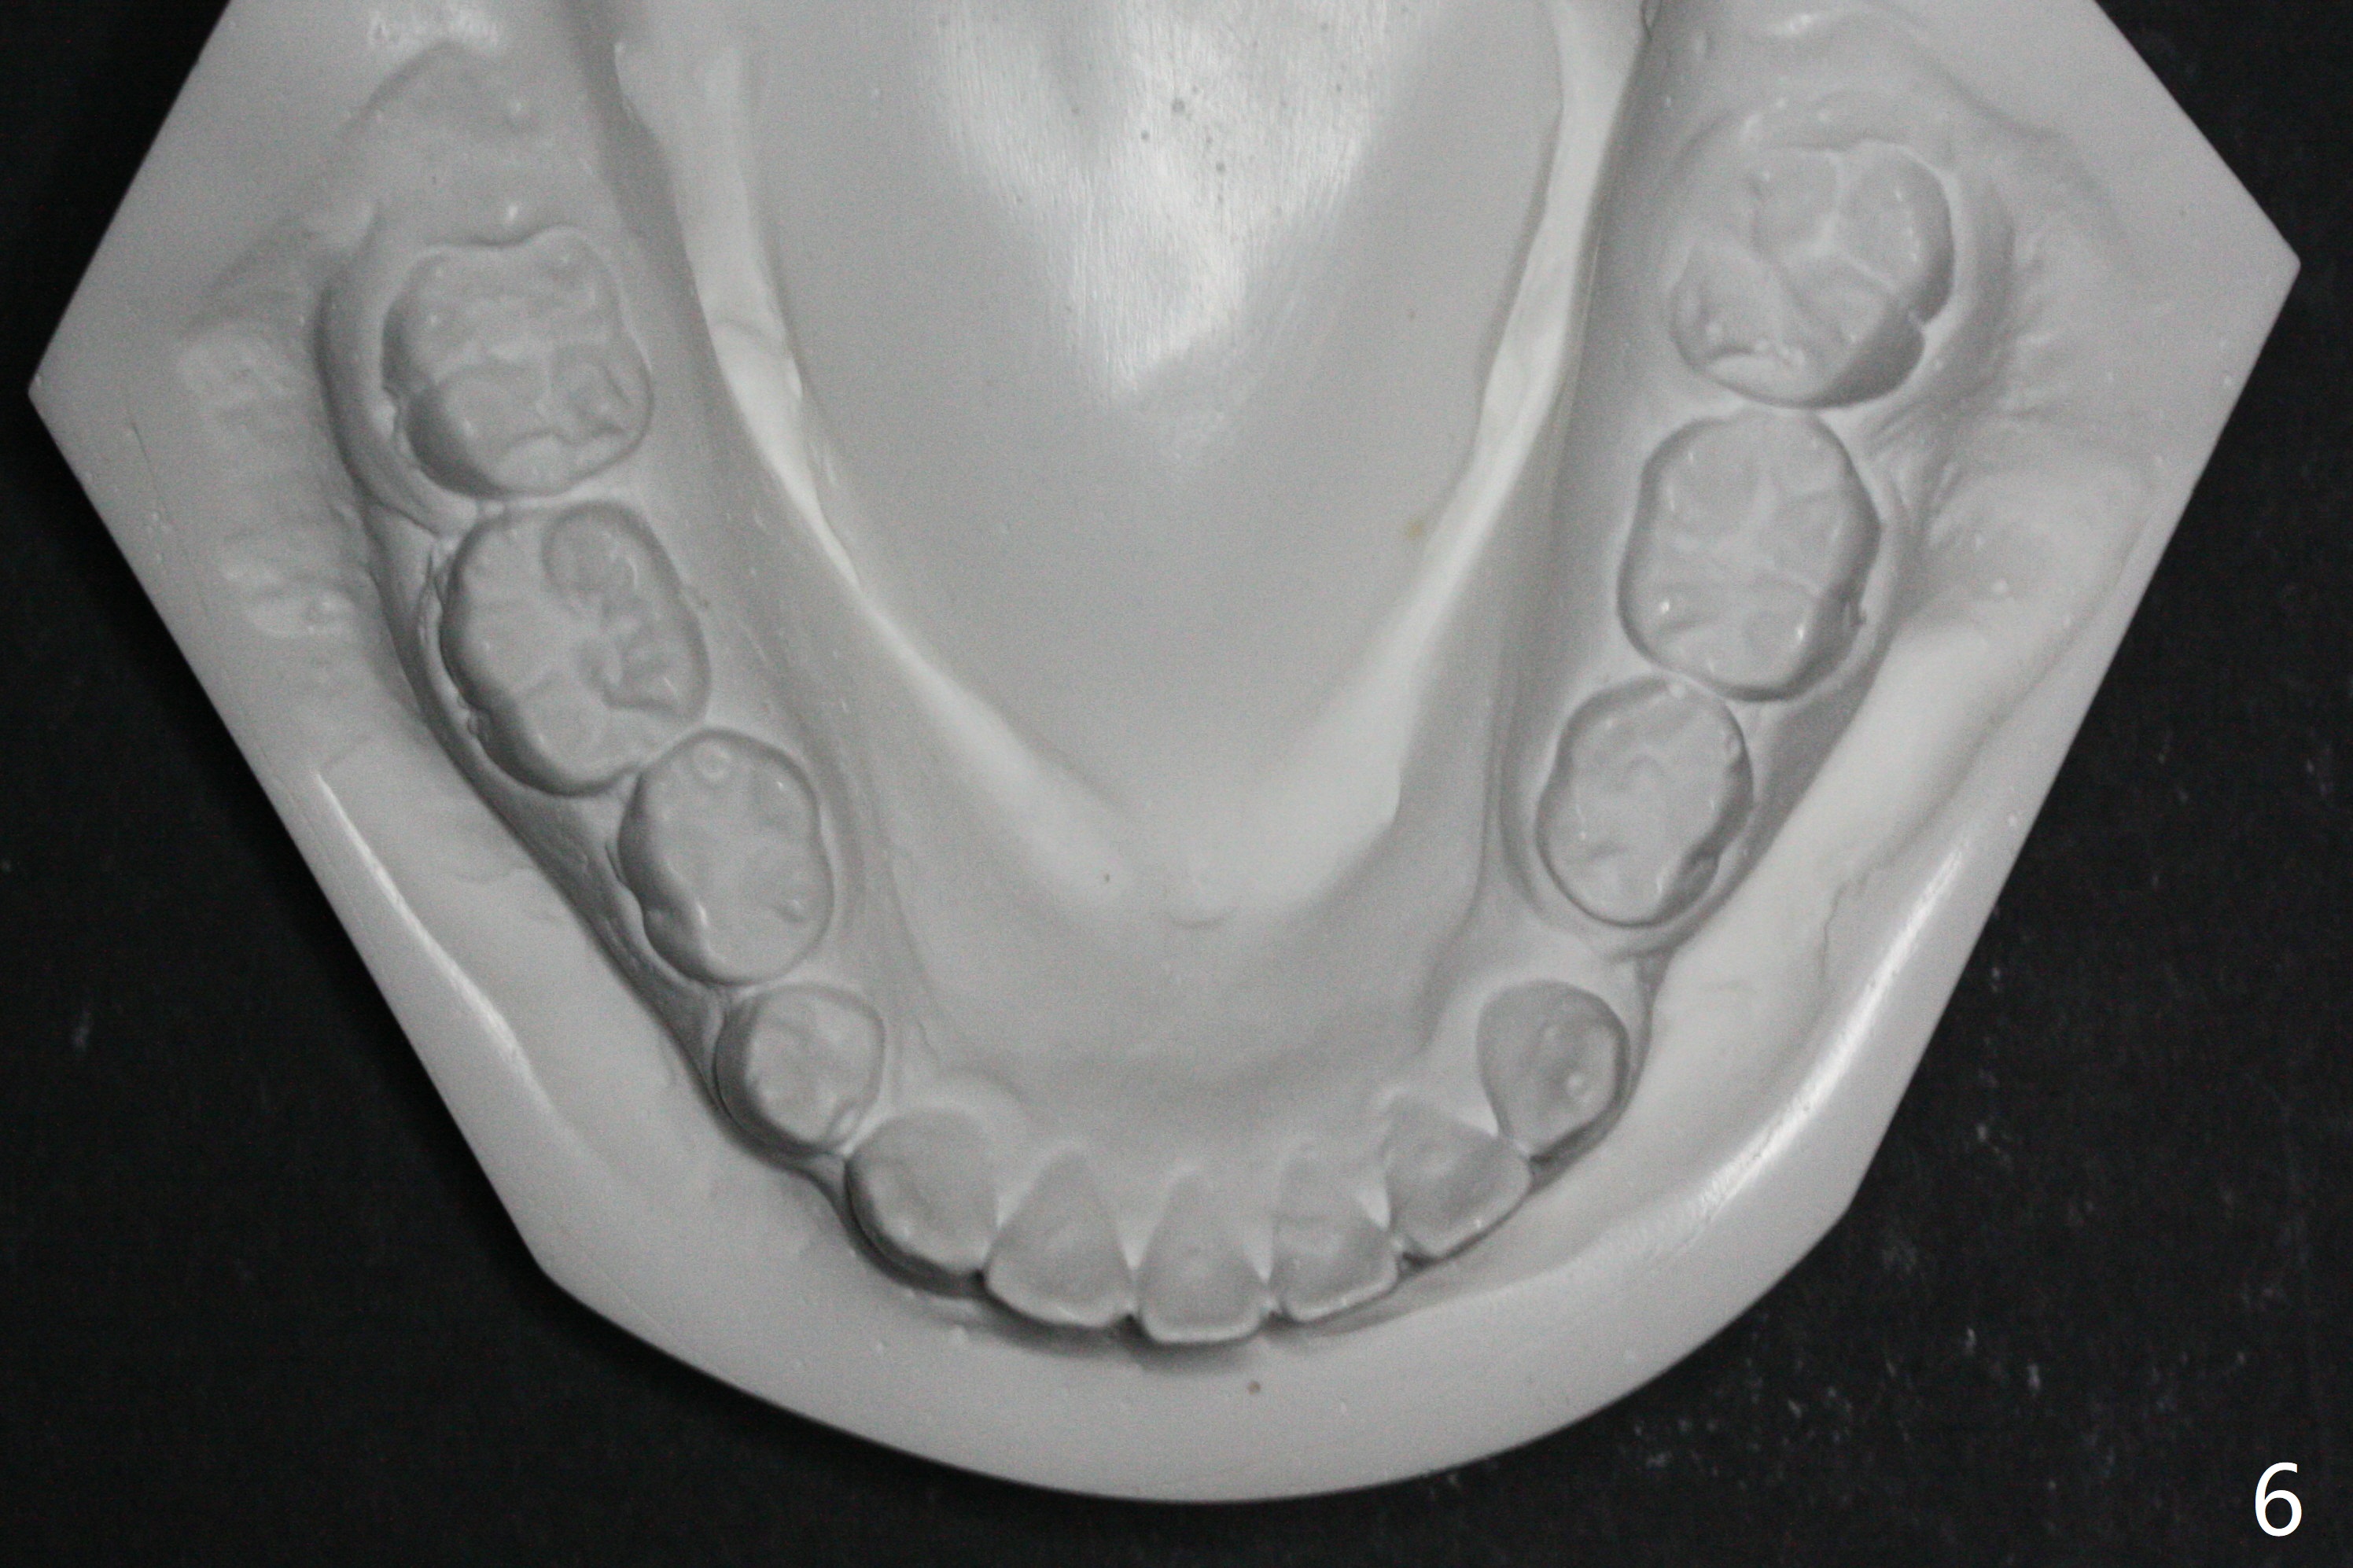

Pre-operative cephalometric X-ray shows convex facial profile (Fig.1). In fact tracing (a few days after banding) shows bimaxillary protrusion (SNA, SNB (88 and 87 degrees vs. 82, 80 (normal)). It appears that extraction orthodontics is indicated (UR4, UL5 (impacted) and LEs). The facial and upper dental midlines seem to coincide (Fig.2). No brackets or bands are placed at UR4 (because of non-cooperative (hyperactive)), LEs (Fig.3,4), or L7s (incomplete eruption, data not shown). Note wire bending between the canines and incisors, as related to correction of overbite. Shrinkable tubes are used in the region without bracket to prevent tissue injury. The upper arch seems to elongate (Fig.5, as compared to the lower one (Fig.6)). It appears that UR4 and UL5 should be extracted for normal profile and alignment. Cephalometric tracing shows that SNA and SNB are 79 and 85º, respectively, suggesting extraction (Fig.7).